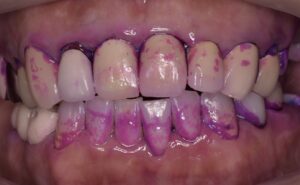

また、大きく削って被せ物をしないと治療報酬的に赤字になるということで、本当に大事な部分を削っては金属で被せてきました。歯を守るための理論を完全に無視した治療(破壊行為?)が平然と行われているのが現状です。そうしないと医院経営ができないような健康保険のシステムが悪いと考えていますが、安かろう悪かろうで通用していました。その結果、上の写真のように、被せ物の縁からは細菌がドバドバ入り、外すと歯がボロボロという悲しい状況がつくられてしまいました。被せ物は丈夫なので、外からはわからないけど、中は腐ってグジュグジュ、という歯を何千本見てきたことでしょう

そこで、最近の世界的(とくにヨーロッパ)な潮流としては、被せ物をせずに、最小限で治療できないか?そして、歯が割れたり、虫歯を再発させないための理論はないか?が活発に議論されています。その結果、築き上げられてきたのが以下のモダンエンドの考えです。